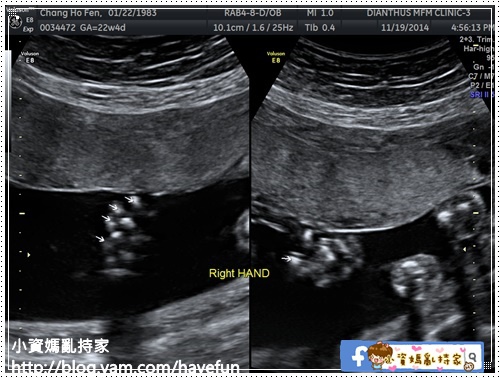

右手的五根手指頭

左手五根手指頭

HL肱骨長:3.65CM

左右前臂的兩根骨頭

FL股骨長:3.7CM

左右小腿的兩根骨頭